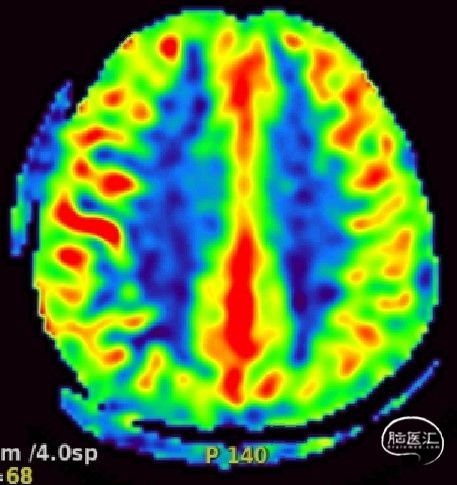

磁共振ASL灌注:左侧大脑半球血流较右侧差:

总结:30年前左侧大脑中动脉分支闭塞,导致左侧额顶叶脑梗塞,遗留右上肢肌力差。本次为右侧大脑中动脉闭塞导致的内分水岭梗塞症状。